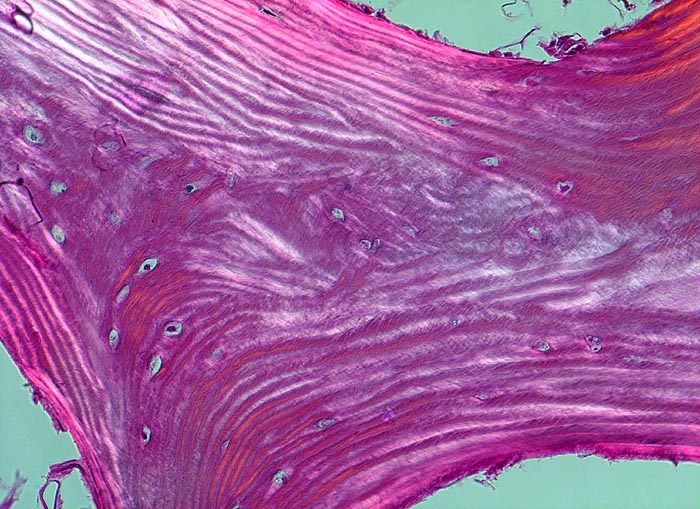

PathoPic ID 4511 - Normale Spongiosa

Normale Spongiosa

Knochen, Tibia

In der Doppelbrechung werden die regelmässig angeordneten Lamellen dieses Spongiosabälkchens besonders gut sichtbar.

200